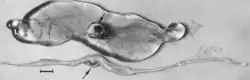

Macroscopic changes of embryos are death followed by resorption of fluids (Fig. 17.4) and then soft tissues (Fig. 17.5). Virus and viral antigen are widely distributed in tissues of infected embryos and their placentas (Mengeling et al. 1980a), and it is probable that microscopic lesions of necrosis and vascular damage, subsequently described for fetuses, also develop in advanced embryos.